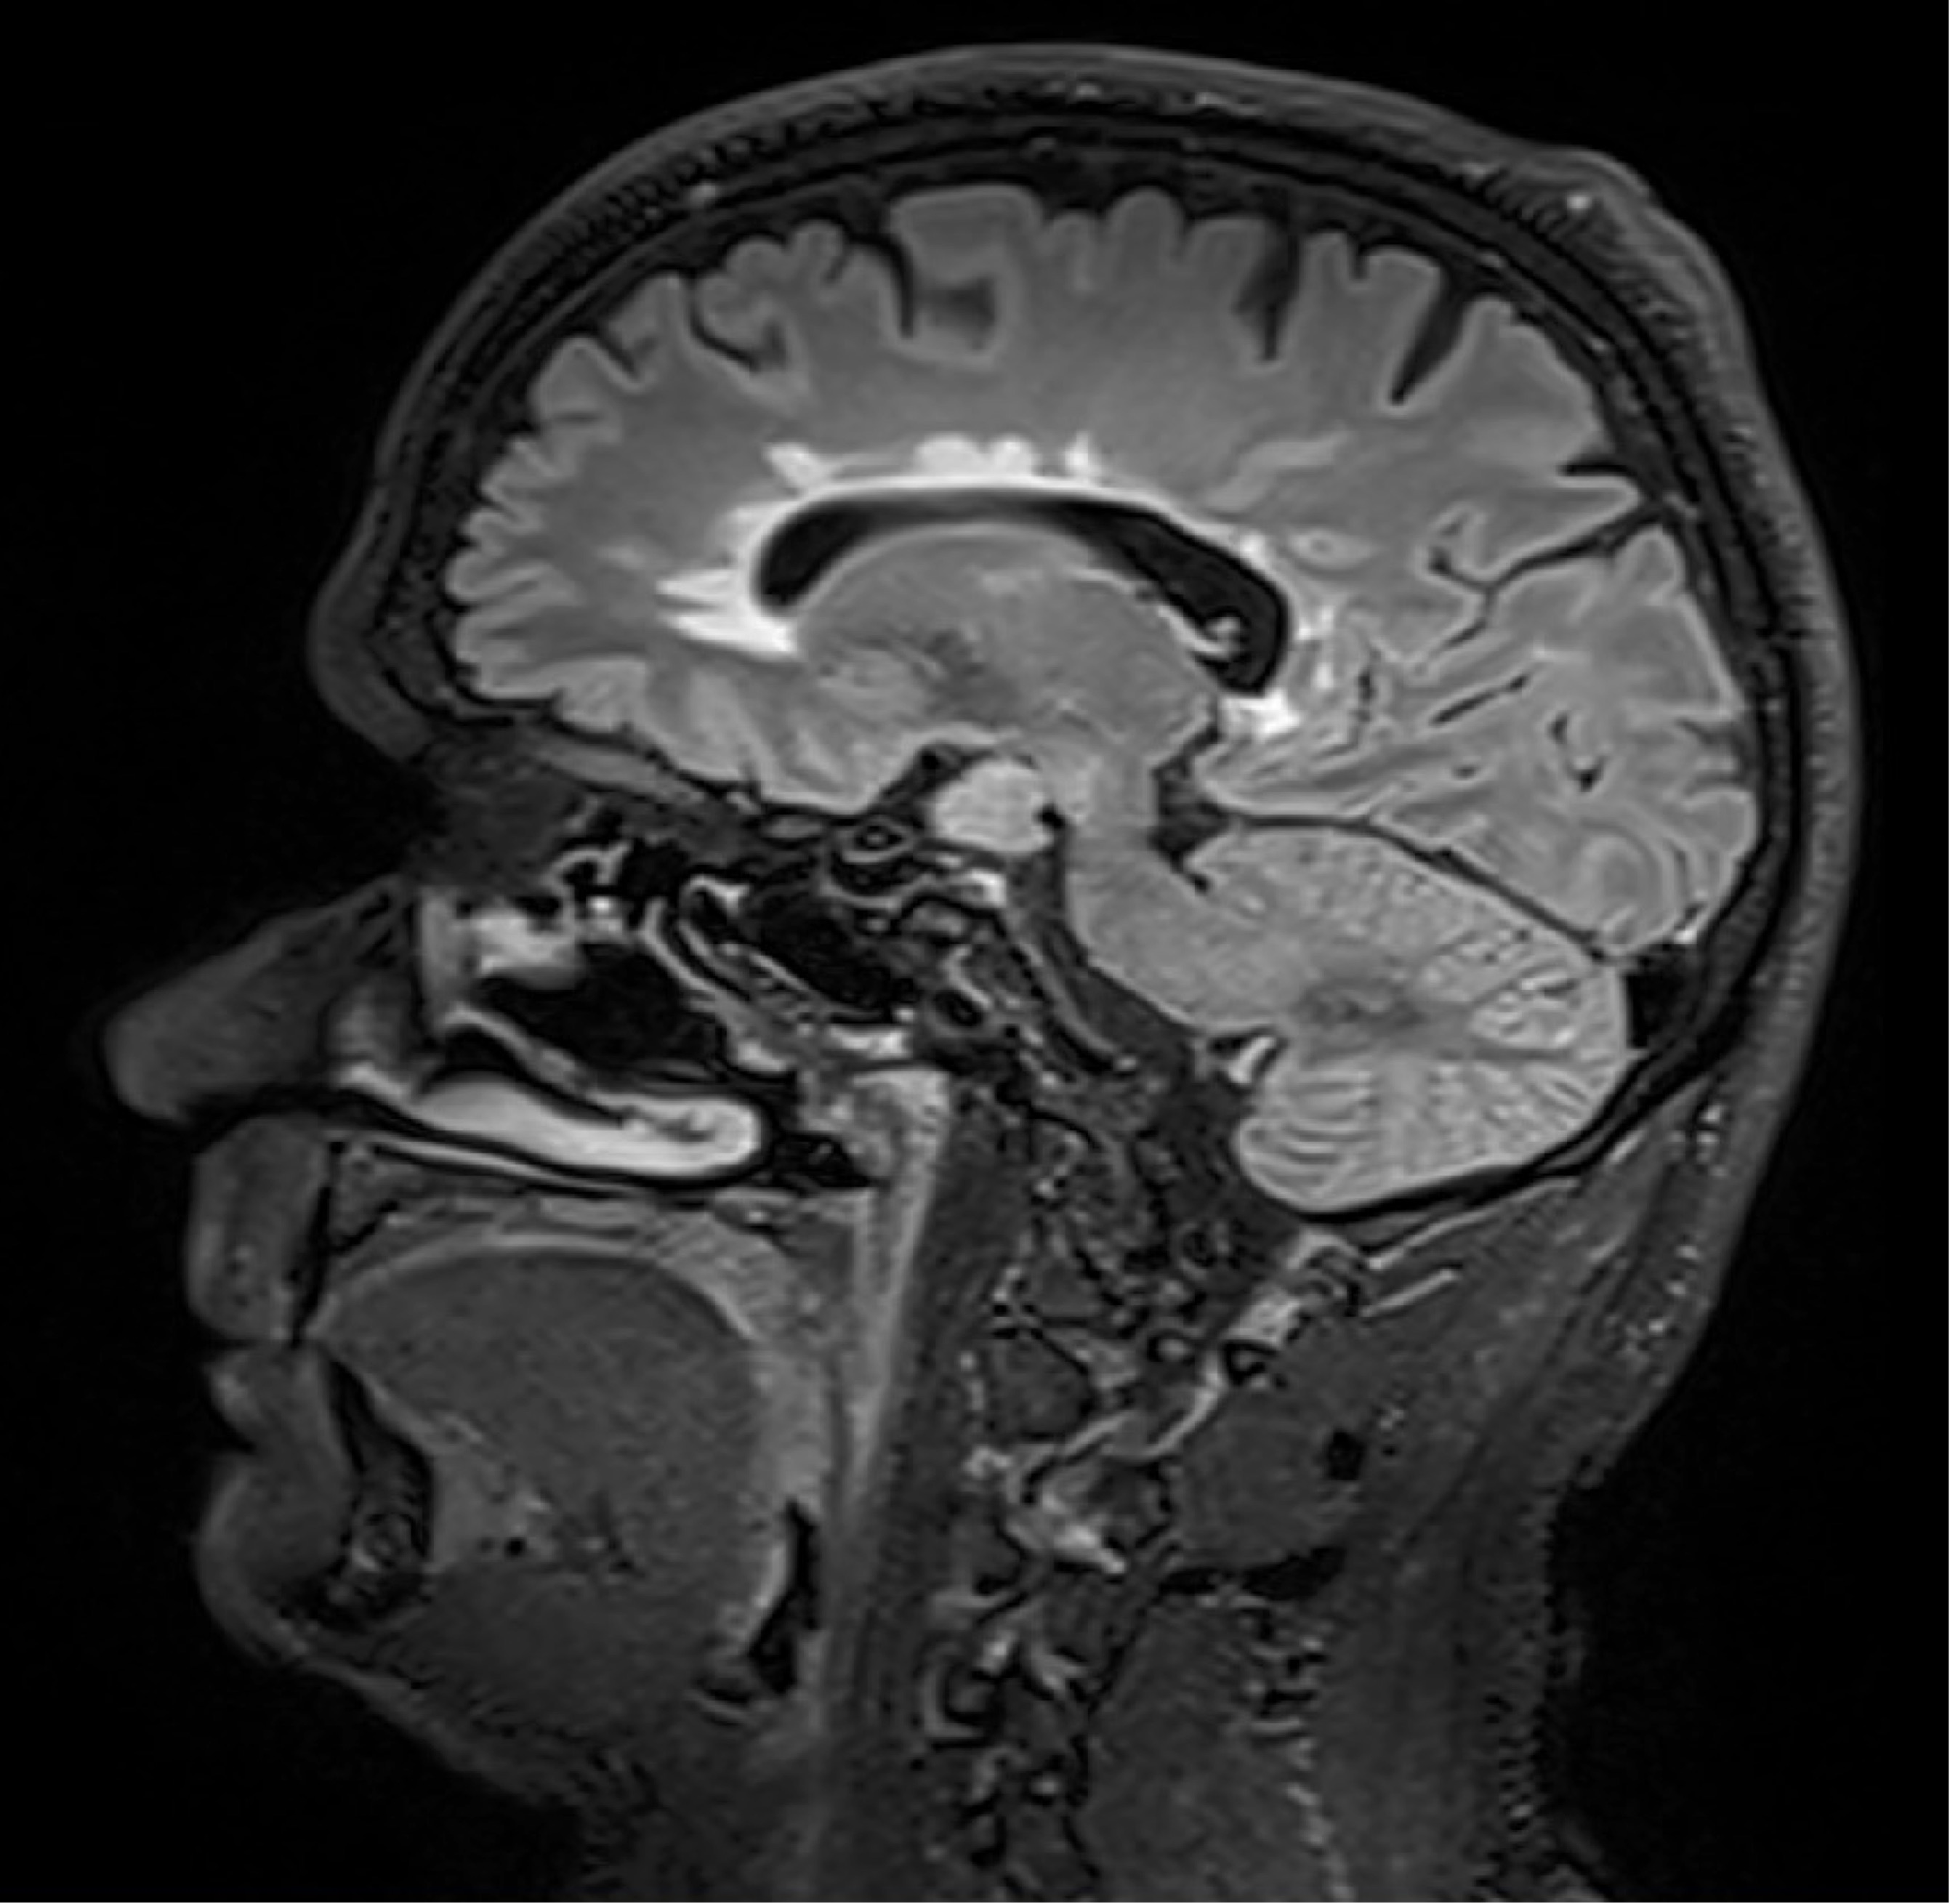

BU: Die Aufnahmen aus der Magnetresonanztomographie zeigen einen jungen Patienten mit Multipler Sklerose mit mehreren entzündlichen Läsionen des Gehirns. (© Radiologie Innsbruck)

Abseits klinischer Symptome, die von Einschränkungen des Sehvermögens bis hin zu Lähmungserscheinungen ein breites Spektrum umfassen, kann die Krankheitsaktivität bei MS auch bildgebend dargestellt werden. „Der Nachweis entzündlicher Läsionen im Gehirn mittels MRTerlaubt auch eine Einschätzung geringerer Krankheitsaktivität, denn vermeintlich stabile Patient:innen können trotz Therapie weiterhin neue, klinisch stumme, entzündliche Veränderungen entwickeln“, weiß Neuroimmunologe Harald Hegen, der an der Innsbrucker Univ.-Klinik für Neurologie bereits seit vielen Jahren zu MS forscht.

In die Studienkohorte wurden 131 MS-Patient:innen aus MS-Zentren in Österreich und der Schweiz eingeschlossen, die unter einer gering- bis moderat-effektiven Immuntherapie zwölf Monate lang klinisch stabil waren und dann einer MRT unterzogen wurden. „Wir konnten zeigen, dass Patient:innen mit schubförmiger MS, die unter Immuntherapie zwei oder mehr neue entzündliche MRT-Läsionen innerhalb eines Jahres entwickeln, auch bei klinischer Stabilität, also ohne Symptome, von einem Wechsel auf eine hoch-effektive Immuntherapie profitieren“, beschreibt Erstautor Gabriel Bsteh von der Medizinischen Universität Wien die zentrale Erkenntnis. Damit liefert die Studie eine für den klinischen Alltag wichtige Erkenntnis, die für die individuelle Therapieanpassung genutzt werden sollte.

„Nachdem Läsionen oft schon vor dem Auftreten klinischer Symptome in der MRT sichtbar sind, ermöglicht eine bildgebende Kontrolle bei Patient:innen mit einer gering- bis moderat-effektiven Therapie ein frühes Eingreifen in den individuellen Krankheitsverlauf“, betont Studienleiter Harald Hegen. In der Studienkohorte waren rund 40 Prozent der Patient:innen klinisch stabil, zeigten allerdings in der MRT schon eine oder mehrere Läsionen. Bislang war in der klinischen Praxis eine Therapieverstärkung nur nach Auftreten klinisch manifester Symptome angezeigt.